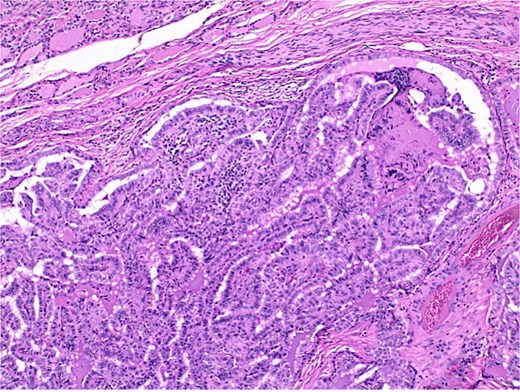

The final pathological report revealed a 1.4 cm classic papillary carcinoma in the isthmus, with extrathyroidal extension, without vascular, lymphatic, or perineural invasion, and with clear margins. In the left lobe, a minimally invasive follicular carcinoma of 3.5 cm was diagnosed, with capsular and limited vascular invasion (less than four vessels), without lymphatic or perineural invasion, and with clear margins (Figs 2–4).

Histological section of papillary carcinoma showing papillary architecture, clear nuclei, and nuclear membrane thickening.

Histological section showing follicular carcinoma in the upper region and papillary carcinoma in the lower region, with intervening non-neoplastic thyroid tissue.